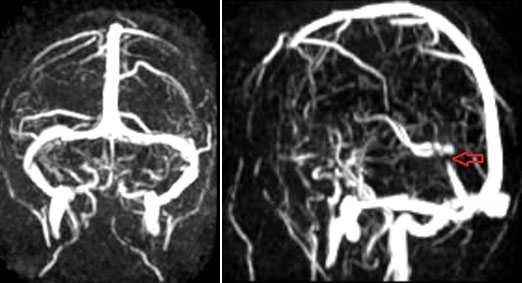

МР-венография - отсутствие визуализации кровотока в правом поперечном синусе и яремной вене.

МР-венография: тромбоз левого поперечного синуса. Отмечается потеря МР-сигнала от левого поперечного синуса.

МР-венография: тромбоз правого поперечного синуса. Отмечается потеря МР-сигнала от правого поперечного синуса.

Тромбоз правого поперечного синуса. Отсутствие феномена «пустоты потока» от правого поперечного синуса на МРТ головного мозга. Отсутствие визуализации правого поперечного синуса на МР-венографии.